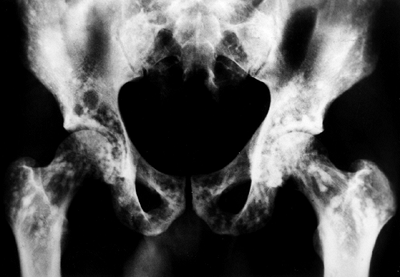

chyloperitoneum, and cachexia (23,88,91,92,93) (Fig. 10.5A).

![]() |

Figure 10.5 A 12-year-old boy with Gorham disease. A: Chest x-ray demonstrates a chylothorax and loss of ribs 8, 9, and 10. B:

The neovascular tissue is bright on T2, and this magnetic resonance image shows extensive vertebral destruction and paravertebral involvement. This boy subsequently died because of the disease. |